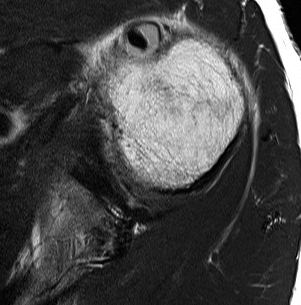

Tendonitis / tendinopathy

Normal

Tendonitis

Tendon thickening / tendinopathy

Sagittal MRI demonstrating severe LHB tendinopathy